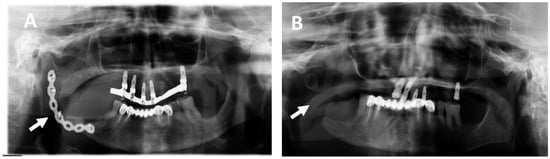

2. Results

2.1. Clinical and Histological Manifestations of the Tumors

4.2. Magnetic Resonance Imaging